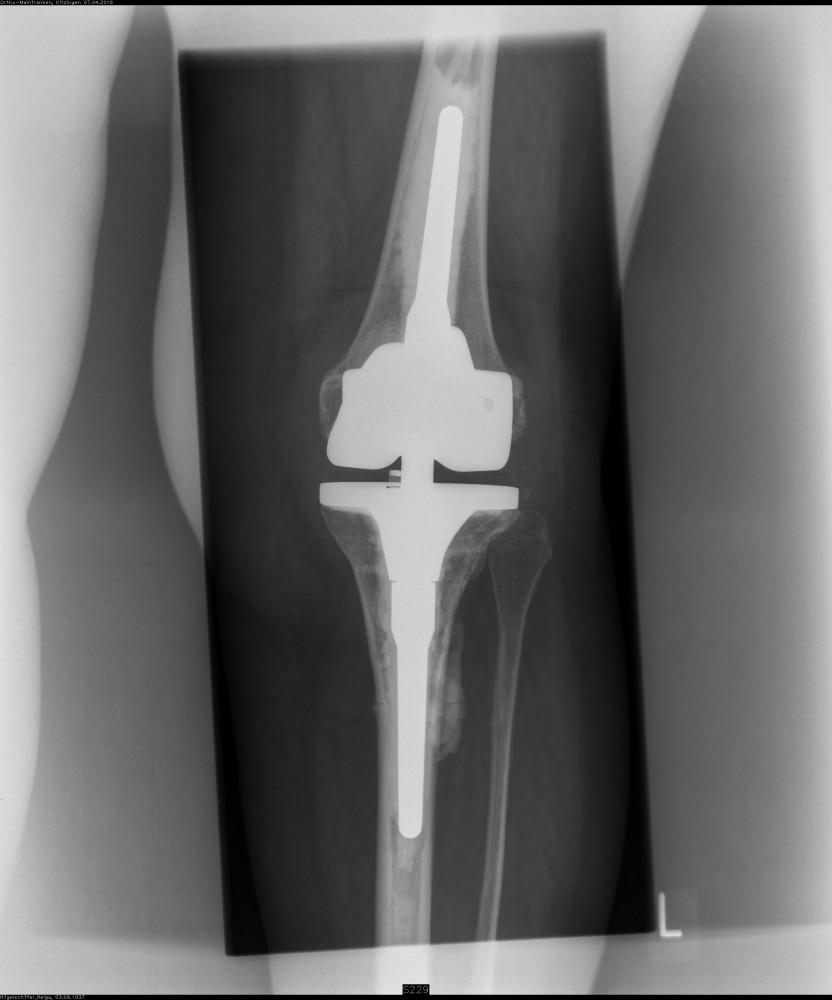

Bei einer starken Fehlstellung und stark gelockerten Seitenbändern des Kniegelenkes muss die Stabilität durch ein Implantat mit Schaftverankerung übernommen werden.

Da es bei diesen Operationen auch zu teilweisem Knochenverlust und resultierender Instabilität kommen kann, sind Revisionsimplantate erforderlich mit denen ein erneuter Aufbau des Gelenkes  erreicht wird.